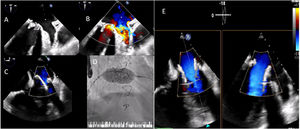

We describe the case of an 85-year-old man who underwent mitral replacement surgery with a biological prothesis (Carpentier-Edwards SAV 29) in 2011. In October 2020, he developed signs of heart failure. An echocardiogram was performed, revealing severe mitral bioprosthetic regurgitation, due to cusp prolapse (Video 1); preserved biventricular systolic function and major pulmonary hypertension. Due to his advanced age, frailty and having undergone previous cardiac surgery, the risk of new surgery was deemed too high. The decision was taken to perform a percutaneous mitral valve-in-valve implantation of a Sapiens 3 Ultra-29. The valve was inserted via transseptal puncture, with transesophageal echocardiogram and fluoroscopy guidance (Video 1). During valve deployment, rapid ventricular pacing was applied. After valve implantation, a small peri-prothesis leak was observed. There was no interference with the adjacent cardiac structures (Video 2); the mean transvalvular gradient was 5mmHg. The patient improved and was discharged five days later.

Biological valves are being used increasingly,3,4 however, their longevity is shorter and the consequently the number of patients with degeneration of bioprosethic valves will increase. The balloon-expandable Sapiens 3 valve is designed to be deployed in a rigid structure, so that the radial force of the balloon expanding valve provides support.2 This procedure should be considered in high surgical risk patients (Figure 1).

(A and B) Severe mitral prothesis regurgitation due to cusp prolapse, jets directed posterior-laterally and to the left atrial appendage; implantation of an Edwards Sapiens 3 Ultra-29 valve, with transesophageal echocardiography (C) and fluoroscopy (D) guidance; (E) final result: no signs of interference in the adjacent cardiac structures; a small lateral peri-prothesis leak was observed.